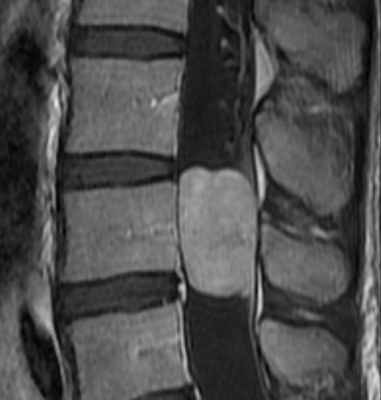

Невриномы (шванномы) и нейрофибромы составляют примерно половину опухолей этой локализации и 35% от всех спинальных опухолей. Гистологически невриномы происходят из шванновских клеток оболочек нерва (леммоцитов), прилегающих к заднему корешку. Обычно диагностируются они в возрасте 20 – 50 лет, у мужчин проявляются несколько в более молодом возрасте, чем у женщин. Они почти всегда одиночные, инкапсулированные, располагаются в любом отделе, но чуть чаще в поясничном или верхнем шейном. Множественные невриномы встречаются исключительно редко при нейрофиброматозе типа II. Нейрофибромы состоят из шванновских клеток и фибробластов, некоторые окружают задний корешок. Они почти всегда множественные и связаны с нейрофиброматозом типа I (болезнь Реклингхаузена). От 2 до 12% нейрофибром перерождаются злокачественно, превращаясь в нейрофибросаркомы. Несмотря на различие в гистологии характер роста опухолей одинаковый. Около 15% из них распространяются в экстрадуральное пространство через одно или несколько межпозвоночных отверстий, приобретая вид “песочных часов”. Такой тип роста особенно типичен для шейной локализации. На рентгенограммах рост по типу «песочных часов» может быть выявлен по расширению межпозвоночного ответстия и эрозии корня дуги. Клинические проявления неврином и нейрофибром состоят в радикулопатическом и миелопатическом синдромах.

На МРТ Т1-взвешенного типа и невриномы, и нейрофибромы изо- или слегка гипоинтенсивны по отношению к спинному мозгу. Однако, встречаются случаи и повышенного сигнала за счет сокращения Т1 мукополисахаридами, связанными с водой. Протонная плотность при МРТ повышена, а на Т2-взвешенных МРТ они чаще неоднородные, могут быть очень яркие участки, где имеется высокое содержание воды, и сравнительно низкого сигнала, особенно в центре. Обе опухоли хорошо контрастируются при МРТ. По форме невриномы округлые, границы ровные, четкие. Нейрофибромы вытянуты вдоль корешка, что лучше видно на корональных МРТ. Размеры могут быть самыми различными.

МРТ грудного отдела позвоночника. Невринома с интра-экстрадуральным типом роста. Корональная Т1-взвешенная МРТ, поперечная Т 1-взвешенная МРТ с контрастированием. Увеличение зоны интереса.

МРТ поясничного отдела позвоночника. Нейрофиброматоз тип I. Множественные нейрофибромы (стрелки). Сагиттальная и поперечная Т1-взвешенные МРТ с контрастированием, корональная Т2-взвешенная МРТ.